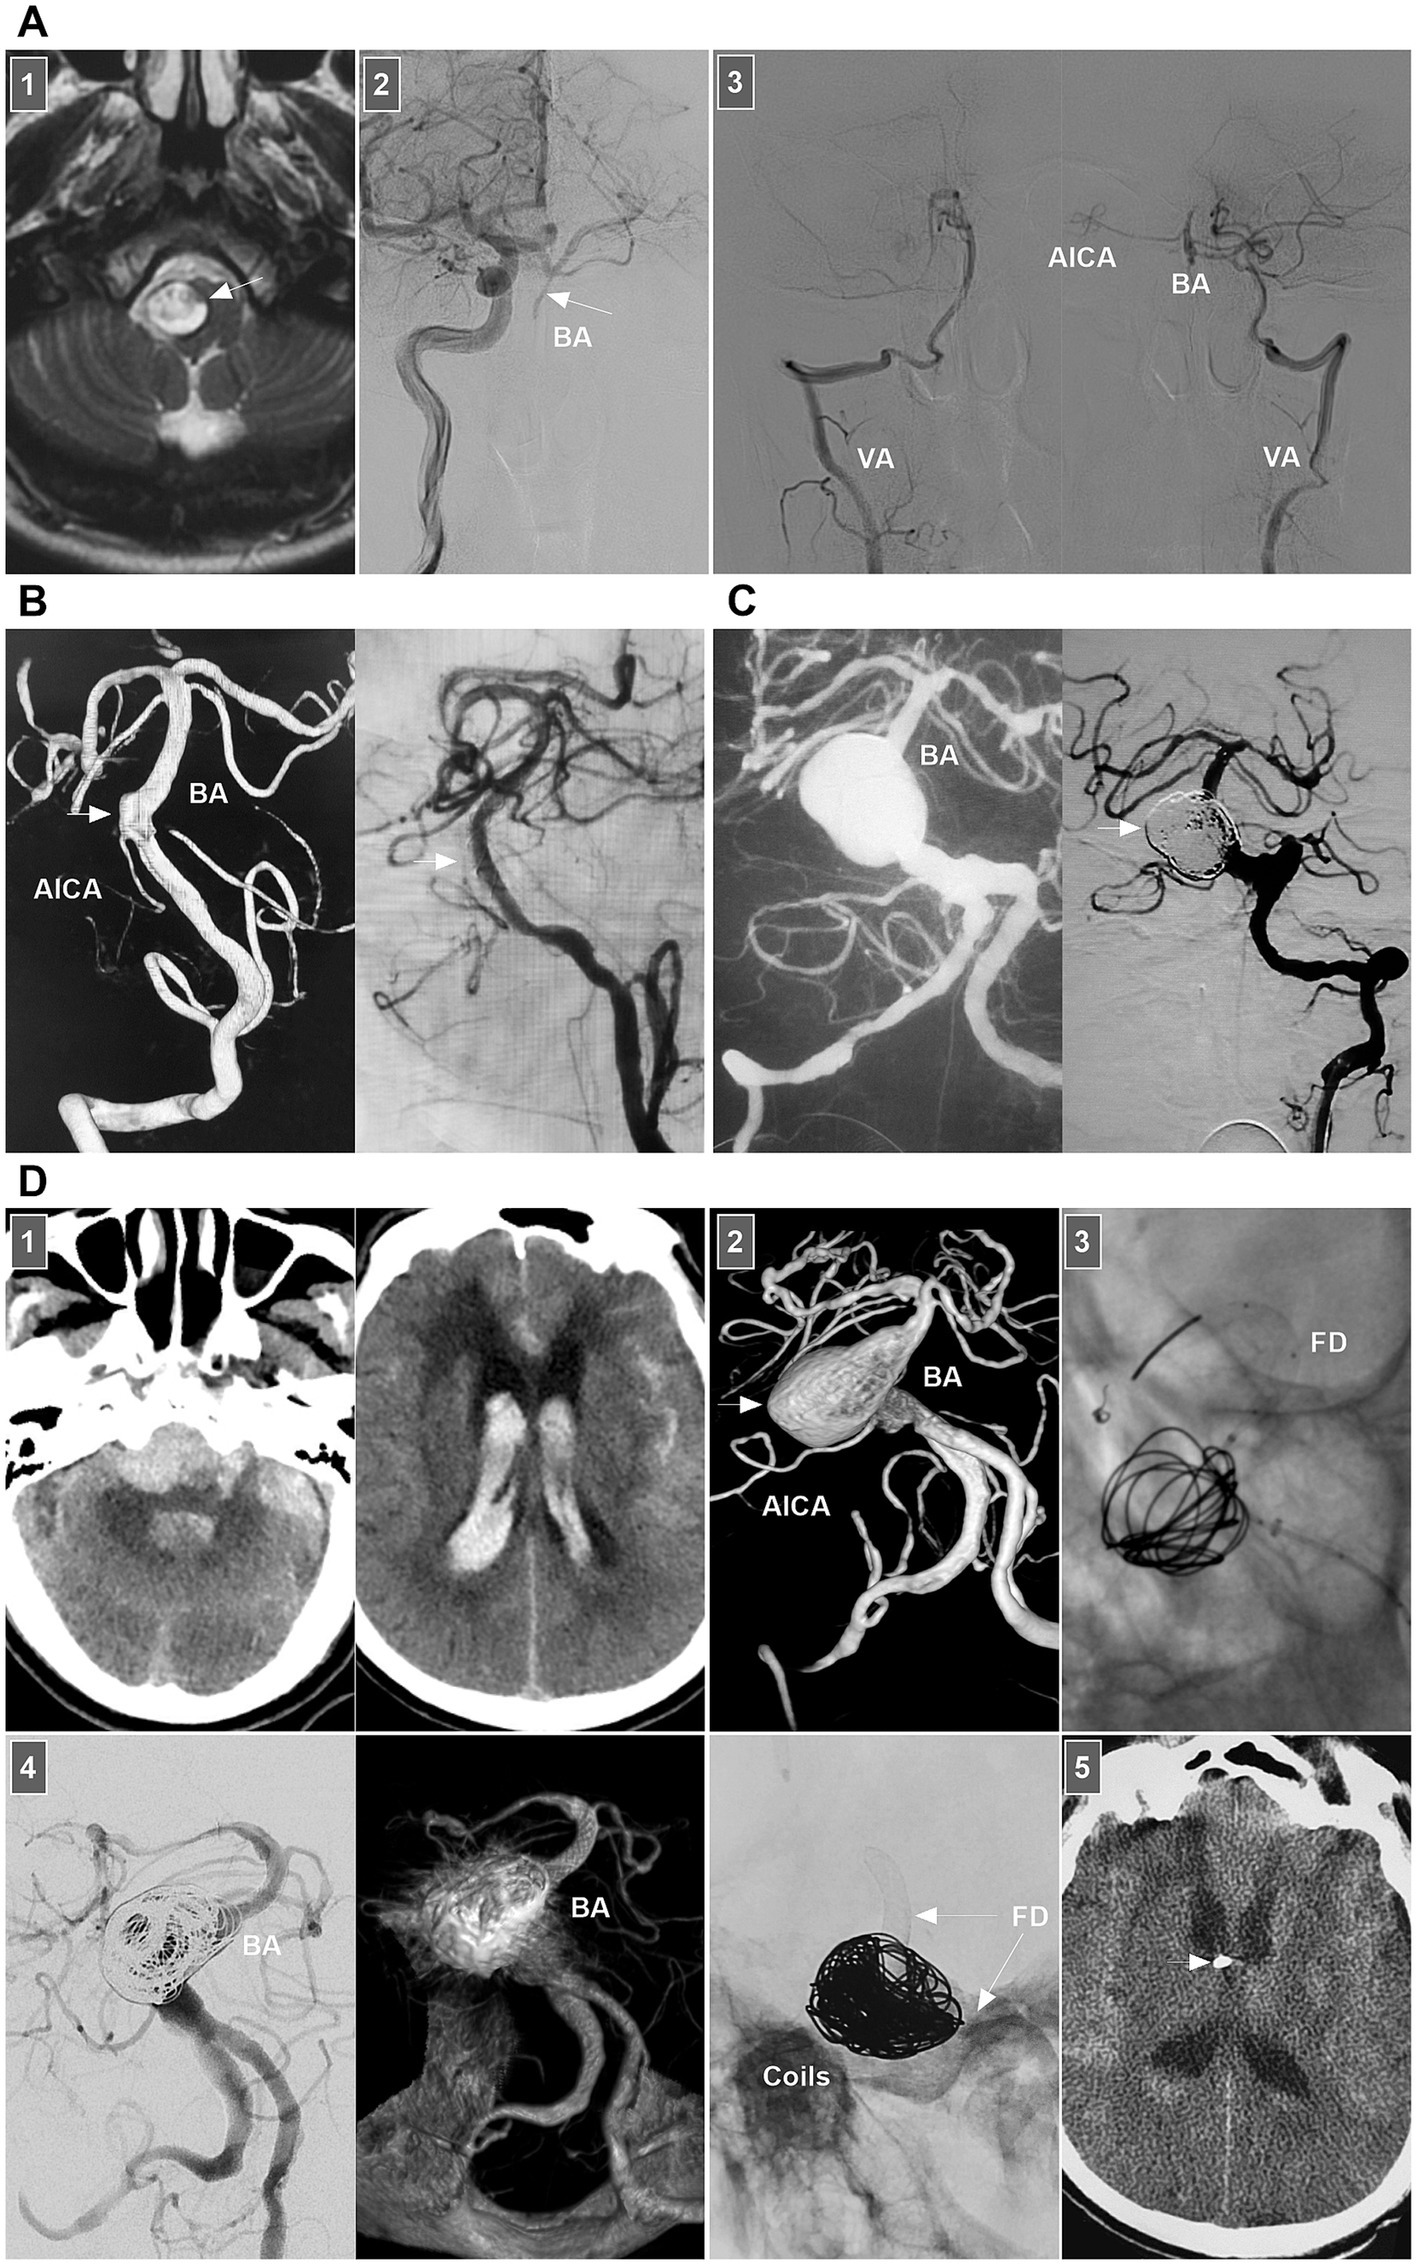

Little is known about the clinical manifestations of spontaneous BA dissections; these lesions may be asymptomatic and silent or may present with SAH, brainstem compression, or ischemia (71). For BA dissections with brain ischemia, conservative anticoagulation treatment is the standard approach. Chronic occluded BA dissection can have no or minor symptoms (Figure 10A) (72). However, acute occluded BA dissection may be associated with high rates of mortality and morbidity. Intervention may be necessary. After aspiration, emergency stenting to reconstruct the BA lumen can be performed (73, 74).

Figure 10

Treatment of BA dissections. (A) Panel 1: Magnetic resonance image showing a lesion (arrow) in front of brainstem. Panel 2: DSA showing the BA was occluded (arrow), the BA tip was supplied by posterior communicating artery. Panel 3: DSA images showing that bilateral VAs only supplied to the PICAs, lower BA and AICA. In the patient, the medication was given. (B) Left panel: DSA showing an unruptured BA dissection (arrow). Right panel: DSA showing delayed appearance of BA dissection after LEO stent deployment. (C) Left panel: Roadmap image showing a ruptured sidewall BA dissecting aneurysm. Right panel: DSA showing the aneurysm (arrow) was coiled under the assistance of traditional stent. (D) Panel 1: CT images (left and right panels) showing subarachnoid hemorrhage and intraventricular hemorrhage. Panel 2: DSA showing a giant BA dissecting aneurysm (arrow). Panel 3: X-ray image showing FD assisted coiling the aneurysm. Panel 4: DSA (left panel) and Vaso-reconstructive image (right panel) showing that the aneurysm was embolized. Panel 5: X-ray image showing the FD (arrows) and coils. Panel 6: Postoperative CT showing the external ventricular drainage (arrow) was performed due to acute hydrocephalus. AICA, anterior inferior cerebellar artery; BA, basilar artery; CT, computed tomography; DSA, digital subtraction angiography; EVT, endovascular treatment; FD, flow diverter; PICA, posterior inferior cerebellar artery; VA, vertebral artery.

For ruptured BA dissection, if the treatment is considered high risk, follow-up can be considered first. When the lesion progresses, aggressive EVT can be used. Chronic BA dissections can present with sidewall, circumferential, or fusiform shapes. For chronic lesions, the optimal management method is unclear. In general, for symptomatic or progressive chronic BA dissections, after the risks and potential benefits of the intervention are balanced, EVT can be considered. Various EVT techniques, including traditional coiling, overlapping stenting, FD deployment or even PAO, can be options (75).

For small or sidewall BA dissections, traditional stenting may be feasible (Figures 10B,C). However, for large or fusiform lesions, the use of FDs seems promising (Figure 10D). Adjunctive coiling for aneurysmal dilatation can prevent rebleeding or aggravate thrombosis; however, mass effects should be considered. In addition, FD deployment can yield hemorrhagic/ischemic complications and an occupying effect. When reconstructive EVT is ineffective for giant BA dissection, flow reversal by occluding bilateral VAs or BA trunk occlusion can be applied in highly selective cases (76). For vertebrobasilar junction dissections below the BA, either FD or traditional stent-assisted coiling can be used (75). The hypoplastic VA can be occluded to avoid contralateral inflow into the dissection site.

8.2.5 AICA dissection

For ruptured AICA dissections with a risk of rebleeding or flow-related dissection with AVMs, EVT may be suggested. The AICA is a small artery that can be divided into the a1–a4 segments (104, 105). The proximal a1 segment sends off brainstem perforators, and the a2 segment sends off the internal auditory artery. Proximal PAO can result in brainstem infarction and hearing loss, and it is the last resort (104, 106). Reconstructive EVT was the preferred choice. Owing to the limitation of the AICA diameter, stenting in the AICA can be employed only for a thick AICA or the common trunk of the AICA-PICA (107). For example, in 2024, Kass-Hout et al. (108) treated AICA dissection with FD [a silk vista baby device (Balt, Montmorency, France)]. PAO is acceptable for distal AICA dissections (Figure 13A).

Figure 13

EVT of AICA and PICA dissections. (A) Left panel: DSA showing a ruptured AICA dissection (arrow). Middle panel: Unsubtracted DSA showing the dissection (arrow) was coiled. Right panel: DSA showing the AICA was patent, and chronic occlusion was worthy to expected. (B) Left panel: CT showing SAH. Middle panel: DSA showing a ruptured PCA sidewall dissecting aneurysm (arrow). Right panel: DSA showing the aneurysms (arrow) was coiled selectively. (C) Panel 1: CT showing the fourth ventricle hemorrhage. Panel 2: DSA (left panel) and its reconstructive image (right panel) showing an AVM that supplied by PICA with flow-related dissecting aneurysms (arrows). Panel 3: DSA (left panel) showing the aneurysms were embolized (arrow), unsubtracted DSA (right panel) showing the Onyx in the aneurysm. Panel 4: Diffuse weighted image of magnetic resonance showing asymptomatic acute ischemia of cerebellar hemisphere. AICA, anterior inferior cerebellar artery; AVM, arteriovenous malformation; CT, computed tomography; DSA, digital subtraction angiography; EVT, endovascular treatment; PICA, posterior inferior cerebellar artery; SAH, subarachnoid hemorrhage; VA, vertebral artery.